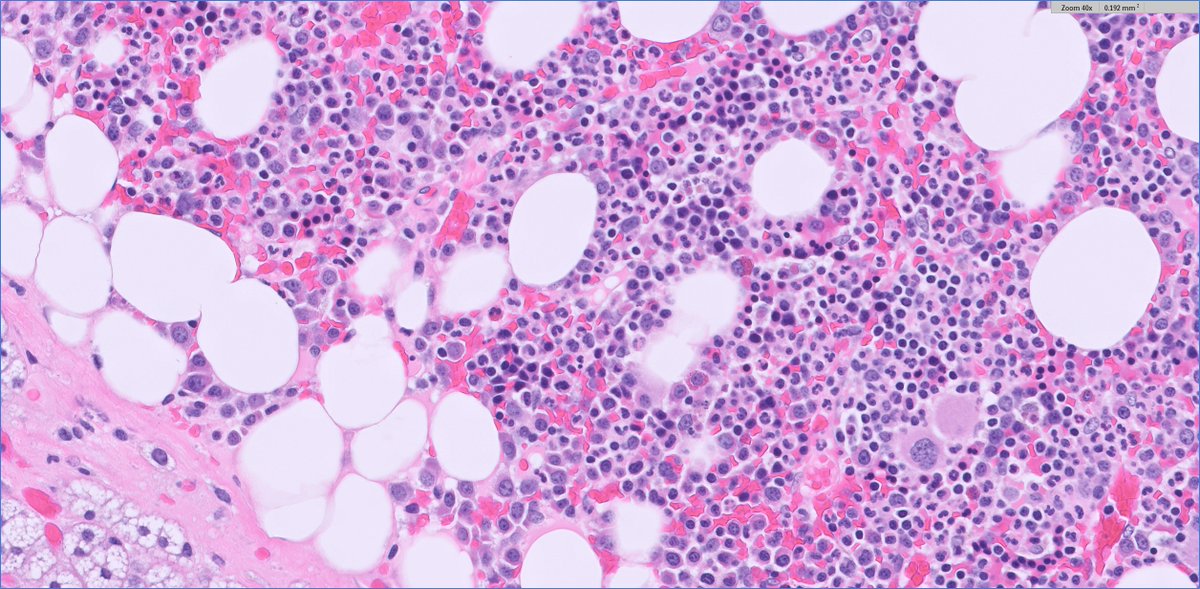

Q for the #endopath folks for this adrenal cortical adenoma (clinical: primary aldo) intratumor/adrenal fat I've seen, perhaps not all that uncommon... but intratumoral/adrenal brown fat? usually I see brown around the peripheral (within background excised fat) when it occurs

intratumor/adrenal fat I've seen, perhaps not all that uncommon...

but intratumoral/adrenal brown fat? usually I see brown around the peripheral (within background excised fat) when it occurs